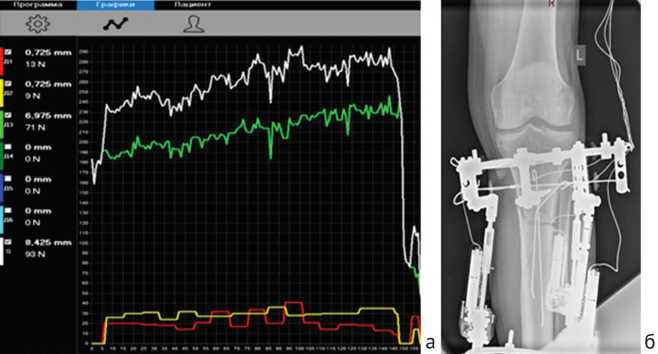

Активный, быстрый рост уровня дистракционных усилий до 200Н позволил врачу уже через два дня увеличить темп дистракции до 3 мм/сут (рис. 3), уровень дистракционных усилий продолжал постепенно подниматься в течение недели.

Рис. 3. Динамика дистракционных усилий в первые шесть дней удлинения: график зеленого цвета отражает динамику усилий ведущего автодистрактора, красный и желтый цвет отражает динамику усилий на ведомых стержнях аппарата, график белого цвета отражает динамику суммарного усилия аппарата Илизарова

а измерение дистракционных усилий показало, что после достижения уровня в 290Н произошло их резкое падение до 20Н, что свидетельствует о нарушение непосредственной связи между костными фрагментами (рис. 4).

Рис. 4. Динамика дистракционных усилий с резким падением уровня сопротивления (а); контрольная рентгенограмма левой голени в день падения уровня дистракционных усилий (б)